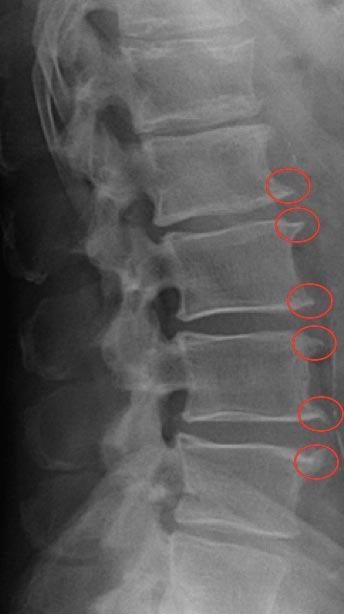

Nós que agradecemos Joanita. O bico de papagaio ou osteófito é um termo muito pesquisado e muitas vezes mal interpretado.